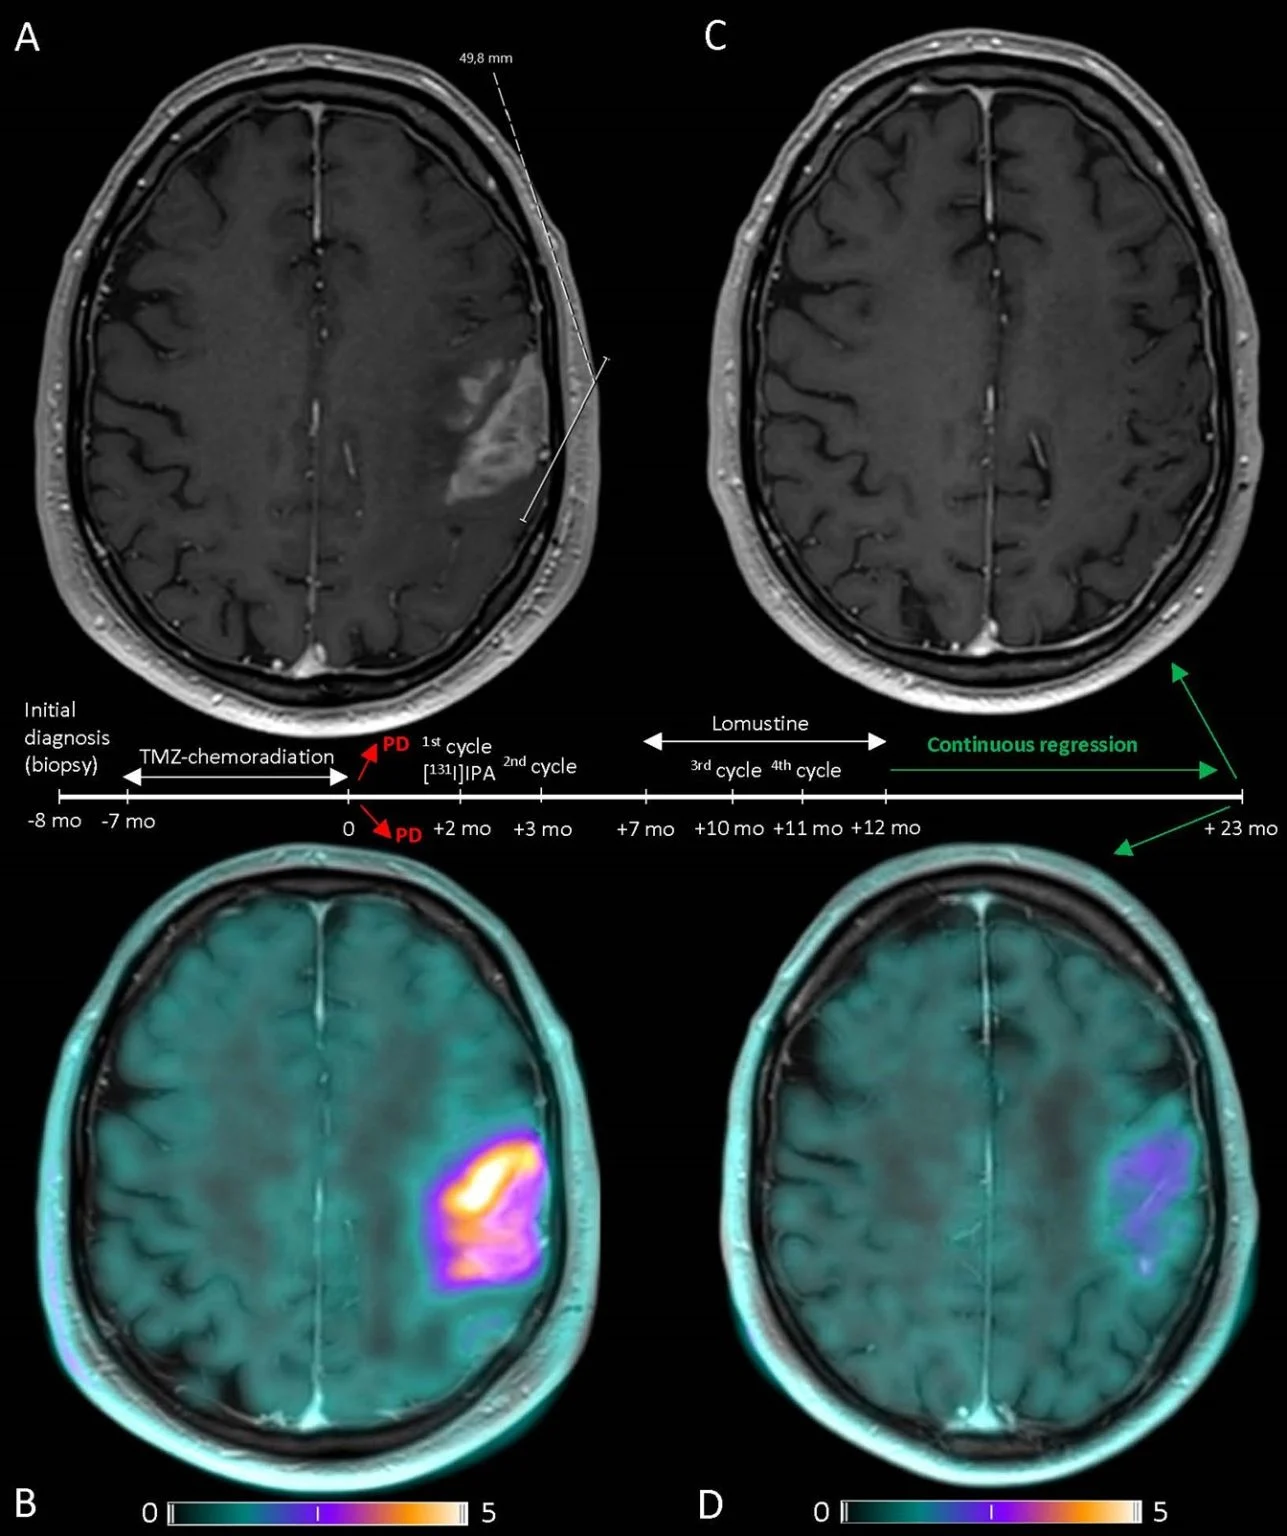

Title: Near complete response recurrent glioblastoma after treatment with [131I]-Iodofalan

The case highlights the promising effects of Iodofalan (131I) ([131I]IPA), a targeted radionuclide therapy, in the treatment of (recurrent) glioblastoma. Several trials on radionuclide therapy, including Iodofalan, are currenlty in preperation or ongoing at UMC Utrecht and internationally!